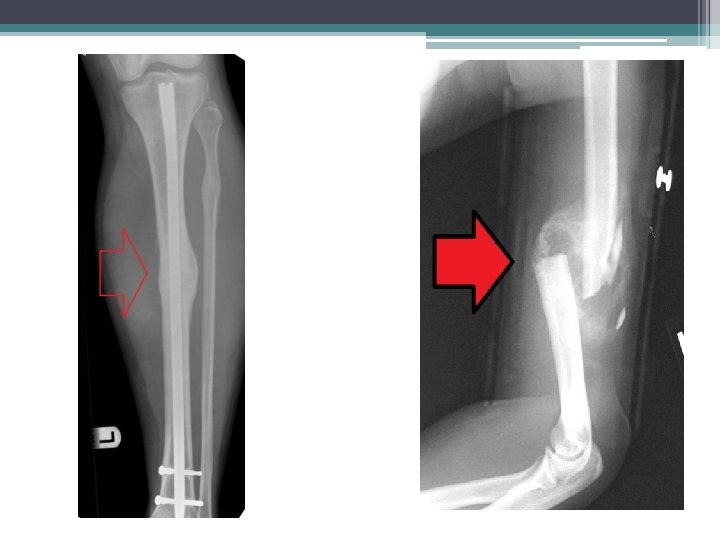

Pathological Fracture in the Humerus before and after fixation